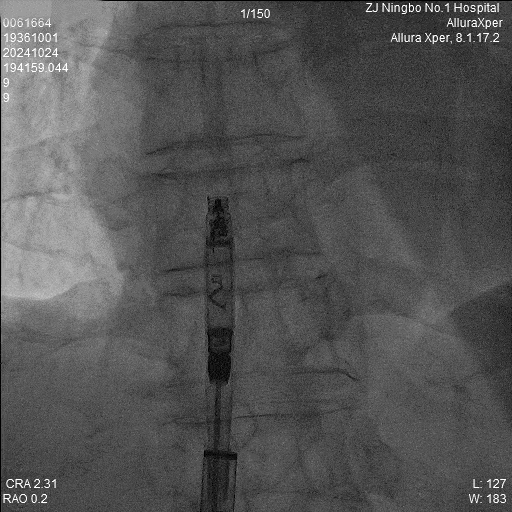

4.旋入起搏器:回撤保护套筒至下腔,释放调弯,调整张力开始旋入旋入0.5圈及1.0圈分别测试参数,等待扭矩传递。